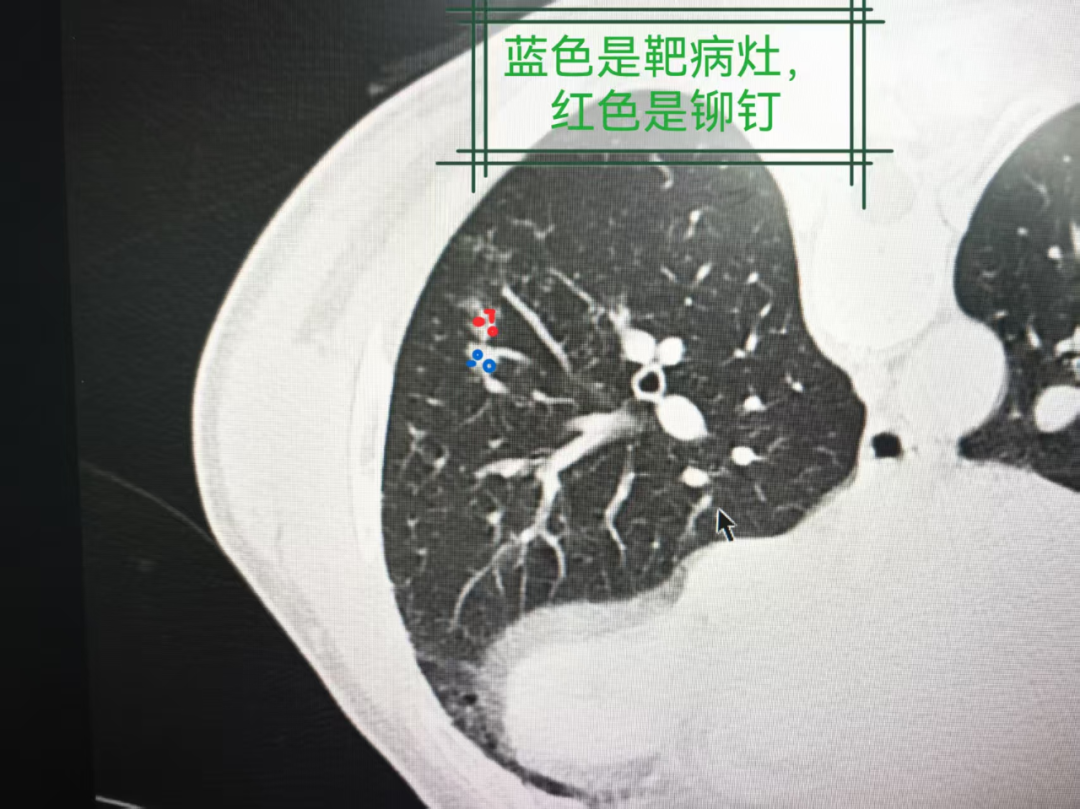

图2:同一CT层面的肺窗图像

图3:同一CT层面的肺窗图像

图4:同一CT层面的肺窗图像